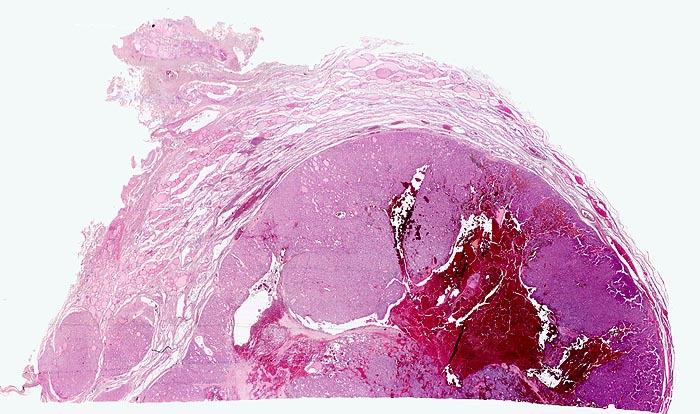

• Anschnitt eines grossen mikrofollikulären Knotens (autonomes Adenom) mit angedeuteter Kapsel und zentraler Einblutung. Oben zwei weitere kleine Satellitenknoten.

• Kompression des angrenzenden Schilddrüsenparenchyms. Dieses besteht aus grossen Follikeln mit kubischem oder abgeflachtem Epithel und reichlich kompaktem dunklem Kolloid in den Follikellumina.

• Zeichen gesteigerter hormoneller Aktivität im Adenom:

• Kleine Drüsenlumina.

• Teils mehrreihiges kubisches bis zylindrisches Epithel.

• Fehlendes oder nur spärliches helles Kolloid mit zahlreichen Resorptionsvakuolen.